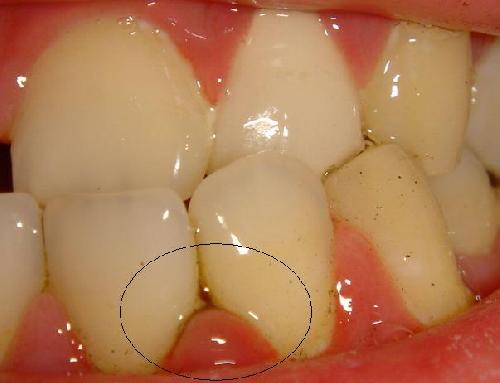

如图, 我的症状是牙龈炎还是牙周炎 或者其他口腔问题.

现在吃肉类,总会塞,把肉剔出来就会流血.

这个部位的牙龈乳头有炎症,可用消炎类药物.局部可涂抹碘甘油不过国外不一定有这种药物.剔牙时尽量别损伤牙龈.别的部位牙龈问题不太大.祝你好运!